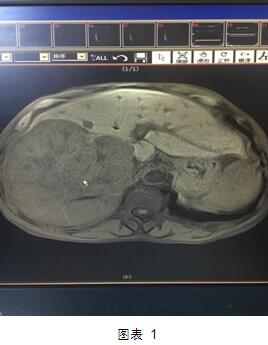

但是近日,我院肝膽外科就做了一次這樣的大挑戰(zhàn)。患者是一位70多歲的老者,老人家入院后診斷為肝右葉巨塊型肝癌(圖1)。這個(gè)癌塊已經(jīng)占據(jù)整個(gè)肝臟的60%,而且腫瘤侵及第一肝門、第二肝門,門靜脈有癌栓形成。這種情況在臨床上已經(jīng)屬于中晚期肝癌,手術(shù)根治困難,風(fēng)險(xiǎn)極大。然而不手術(shù)切除的話,老人家的生存期恐怕不會(huì)超過三個(gè)月,而且會(huì)一直處于癌癥的折磨之中。